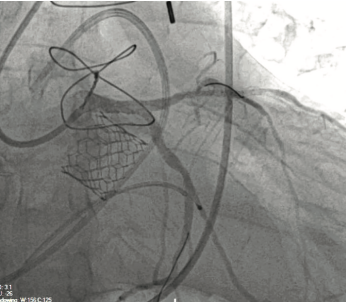

Door-to-Valve Time of 120 Minutes for Severe Aortic Insufficiency and Cardiogenic Shock in ACS

Severe aortic insufficiency in the setting of acute coronary syndrome (ACS) can manifest in cardiogenic shock requiring immediate intervention due to the progressive rise in the left ventricular end diastolic pressure (LVEDP) and hemodynamic instability. There are limited data demonstrating the safety of emergent valve-in-valve (ViV) transcatheter aortic valve replacement (TAVR) for patients presenting with decompensated aortic insufficiency of a failed aortic homograft in the setting of acute coronary syndrome. Our case demonstrates the feasibility of emergent TAVR combined with left main (LM) bifurcation percutaneous coronary intervention (PCI) within 2 hours of hospital presentation for ACS and chronic bioprosthetic aortic insufficiency of a failed homograft with no time for any preoperative planning.